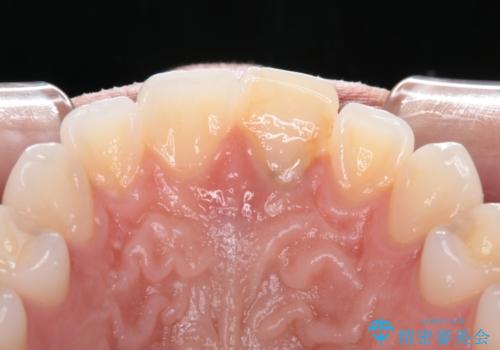

ぶつけて変色した前歯 オールセラミッククラウン治療

- 以前ぶつけて神経を取り除いてから、徐々に変色してきた前歯が気になるとのことで来院された患者様です。

神経を取り除いた歯の変色はホワイトニングでは十分に改善できないため、オールセラミッククラウンにて補綴治療を行うこととしました。

定期的にホワイトニングをされていることや、前歯の歯列が左右非対称であることから、色合いや形態の修正が多くなることが予想されたため、オーダーメイドタイプのグレードを選択していただき、治療を進めて行くこととしました。

予想通り色と形の修正が多く必要となりましたが、最終的には納得のいく仕上がりとなりました。